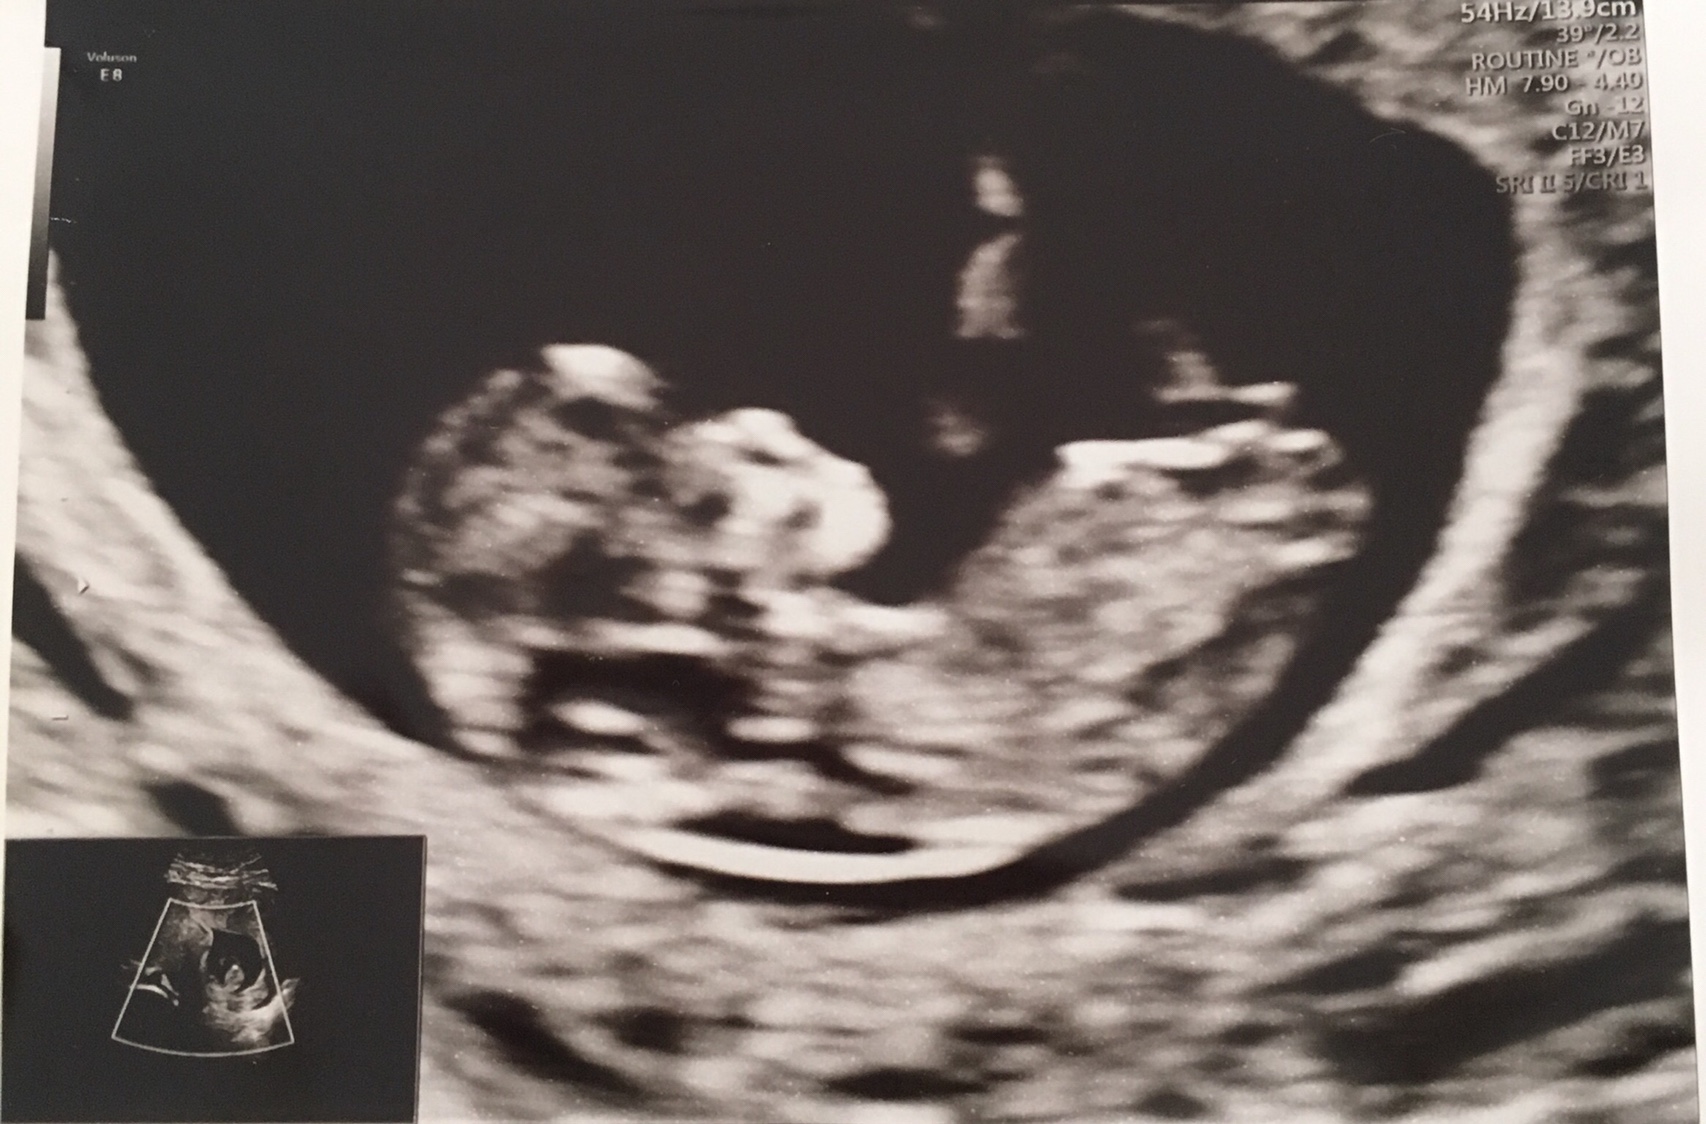

Taken at 11+3, I know that’s still early but no more scans for 3 weeks! Guesses welcome.